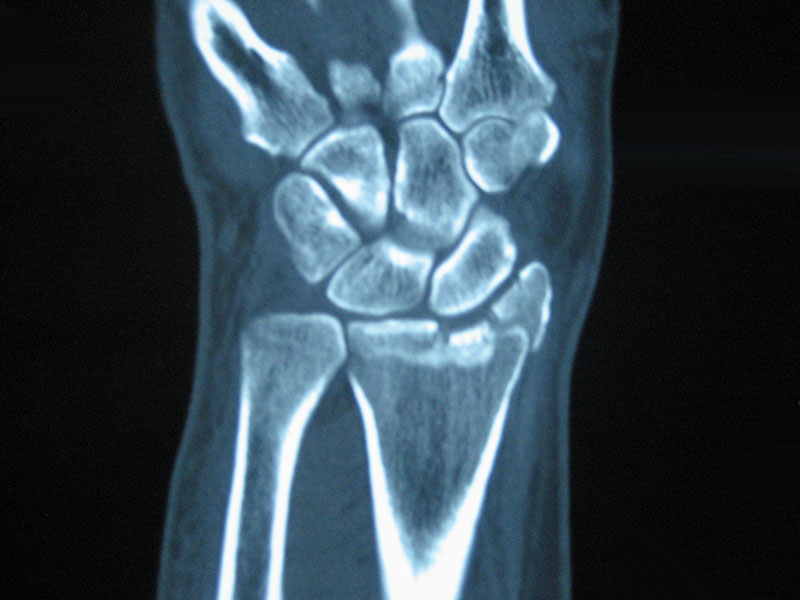

Wrist fractures are very common injuries. This usually refers to a fracture of the radius, the larger of the two forearm bones just before the wrist joint. They tend to occur in two age groups.

In the young adult they are often high-energy injuries (e.g. motor vehicle accidents, sports) and in the older age group, lower energy (e.g. simple fall). A fall onto an outstretched hand is a common story. The joint may or may not be involved in the fracture.

They are often referred to as Colles fractures.

(Example of CT Scan showing disruption of the joint surface of the radius)

The decision on which method of treatment is often made on regular x-rays but in some cases a CT scan may be obtained to get better 3-dimensional information, especially when the joint is involved. The aim of treatment is to reduce disability and restore motion and strength. Even with the best treatment, some people don’t regain full function.